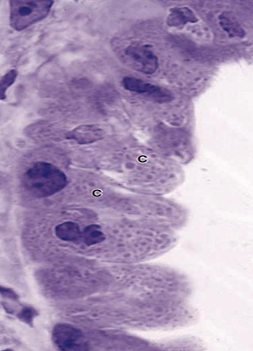

TEM photo of cells lining small bronchiole:

cubical ciliated cells and Clara cell

Identify labeled cell, sites and one specific feature?

Clara cell , mucosa of bronchiole, dome shaped apical surface and secretory granules